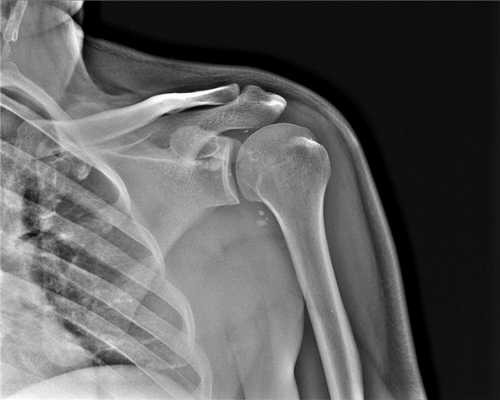

Плечевой сустав. Рентгеновский снимок может потребоваться при подозрении на плечелопаточный периартрит, а также опухолях, воспалительных и дегенеративных процессах, переломах и вывихах. Снимок позволяет также визуализировать ключицу и лопатку.

Когда КТ плечевого сустава лучше, чем МРТ плеча

Компьютерное рентгеновское исследование плеча больше рекомендовано при проведении диагностики костной составляющей человеческого организма, а именно: травматических повреждений костей плеча человека; неправильно сросшиеся кости, наличие костных шпор; поражений костей опухолевой природы как первичных, так и вторичных; атеросклеротических изменений сосудов.